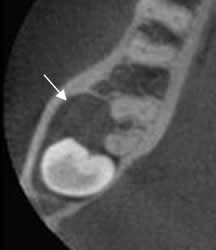

Fig 60. Quiste dentígero.

TAC axial. Lesión quística y excéntrica a las raíces del molar, secundario a quiste dentígero.